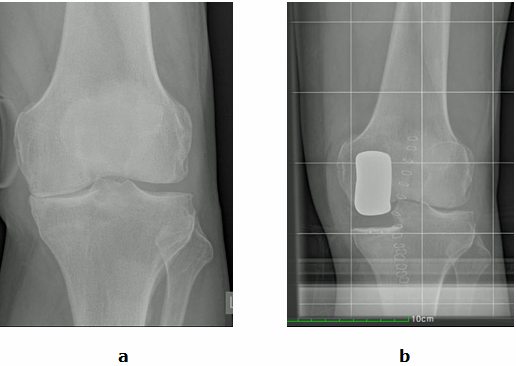

Abb.1: a Der Innere Gelenkspalt (Pfeil) ist aufgehoben. Der Äußere Gelenkspalt ist intakt.

b Der Innere Gelenkspalt wurde durch eine Schlittenprotheseersetzt (Gelenkteilersatz).